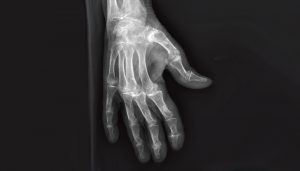

Une chondrocalcinose articulaire invalidante

Madame G., âgée de 95 ans, est admise en médecine interne gériatrique à la demande de son médecin traitant pour un bilan d’altération de l’état général. Des douleurs articulaires invalidantes…